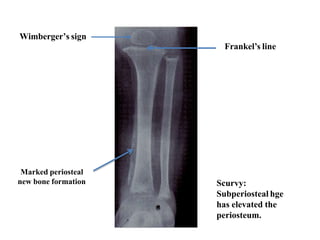

1. Wimberger’s sign-Epiphyses is small,sharply

marginated by sclerotic rim

2. white line of Frankel-Zone of provisional calcification

is dense

3. Trumerfeld zone-a lucent zone

4. Pelkan’s spur

Scurvy. The margins of the epiphyses are sclerotic . There is a

narrow epiphyseal plate, with increased density of the zone of

provisional calcification. Lucent zone beneath this is

trumerfeld zone.

Scurvy:

Subperiosteal hge

has elevated the

periosteum.

Wimberger’s sign

Frankel’s line

Marked periosteal

new bone formation